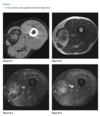

Q

39 yo man fall

Axial T2 fat sat MR - bone contusions in medial patella and lateral femoral condyles (Arrows) with associated tear of medial retinaculum (Arrowhead)

Diagnosis: Acute patellar dislocation relocation

Occurs with internal rotation of femur on fixed and externally rotated femoral condyle - bone contusions on both.

Due to direct impaction, associated with ACL tears.

Radiographs = Lipohaemarthrosis or chip fracture adjacent to donor site of medial facet of patella.

MR findings = Disruption or sprain of the medial retinaculum, lateral patellar tilt or subluxation, lateral femoral condylar and medial patellar osseous contusions. Osteochondral injury to medial patella or lateral femur.